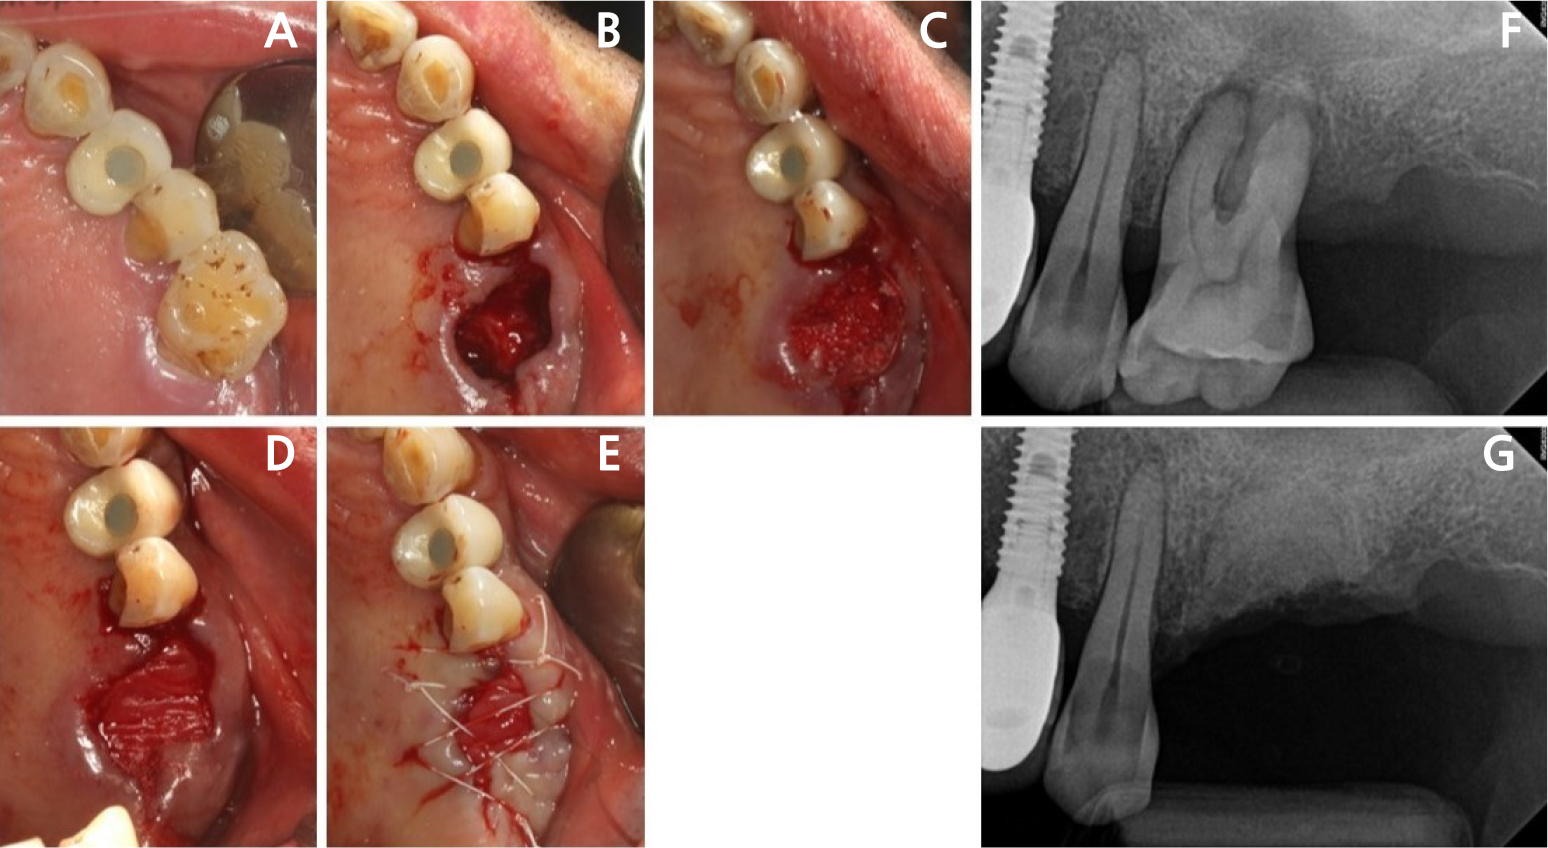

- Retrograde peri-implantitis (RPI) is a localized inflammatory lesion around the apex of a dental implant, typically occurring shortly after implant placement or …

- Retrograde peri-implantitis (RPI) is a localized inflammatory lesion around the apex of a dental implant, typically occurring shortly after implant placement or prosthetic loading. This report describes the clinical management of RPI in a 62-year-old female patient who presented with tenderness and a sinus tract in the mandibular canine region. Radiographic examination confirmed a periapical radiolucency around implant #43, with intact crestal bone. A reconstructive approach was employed through a buccal window following flap elevation. Granulation tissue was removed, and implant surface decontamination was performed using a titanium brush and adjunctive tetracycline hydrochloride scrubbing. The defect was grafted with deproteinized porcine bone mineral and covered with a collagen membrane. Healing progressed favorably, with symptom resolution and radiographic bone fill observed at the 1.5-year follow-up. This case demonstrated that, when appropriate defect morphology and surgical access are present, RPI can be effectively treated using a reconstructive approach. Preoperative cone-beam computed tomography is essential to assess accessibility, and regular periapical monitoring is advised for patients with prior endodontic pathology to enable early diagnosis and intervention. - COLLAPSE